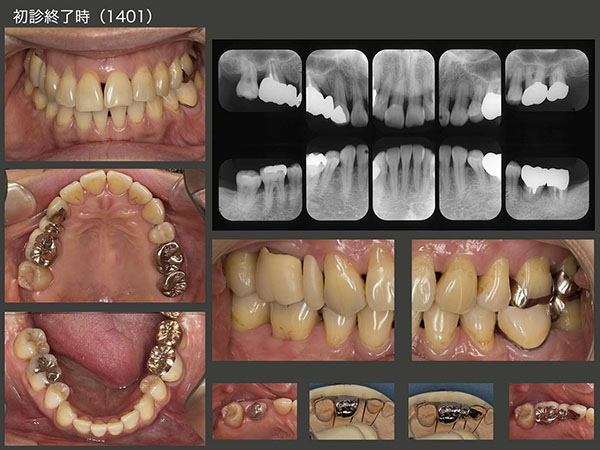

2011年11月初診,37歳女性.右上6が腫れたとのこと.この歯は歯周ポケットが5〜8mmあり,動揺も著しく保存不可能と診断した.患者さんは,歯科矯正のために第1小臼歯を4本抜歯しており,なおかつ右上5,左下6も失っていたが,今回さらに右上6が加わった.

2014年1月,初診終了時の状態.左下6の移植歯は動揺がみられたため,左下7と連結固定した.同部に,フロスが入らないのが難点である.右上は,犬歯と移植歯との間に半歯分のスペースが残ってしまった.このままスペースを残したままという選択肢もあるが,患者さんは望まなかった.しかし,バージントゥースである右上3を削って,ブリッジにするのは抵抗がある.そこで,神奈川県で開業しているN先生に以前教えていただいた方法を採用した.すなわち,右上6(移植歯)は硬質レジン前装冠の近心にグルーブを細工し,セメント合着した.右上3は歯を一切削去せずに,補綴装置を接着性セメントで付けた.こうしておけば,何時か右上3とポンティックの部分の補綴装置は外れるが,その時また接着すればすむ.すごく良い方法であるが,年がら年中外れてしまっては困る方法でもある.実際,14年11月に1回外れたが,その後は何とか外れないでいる.